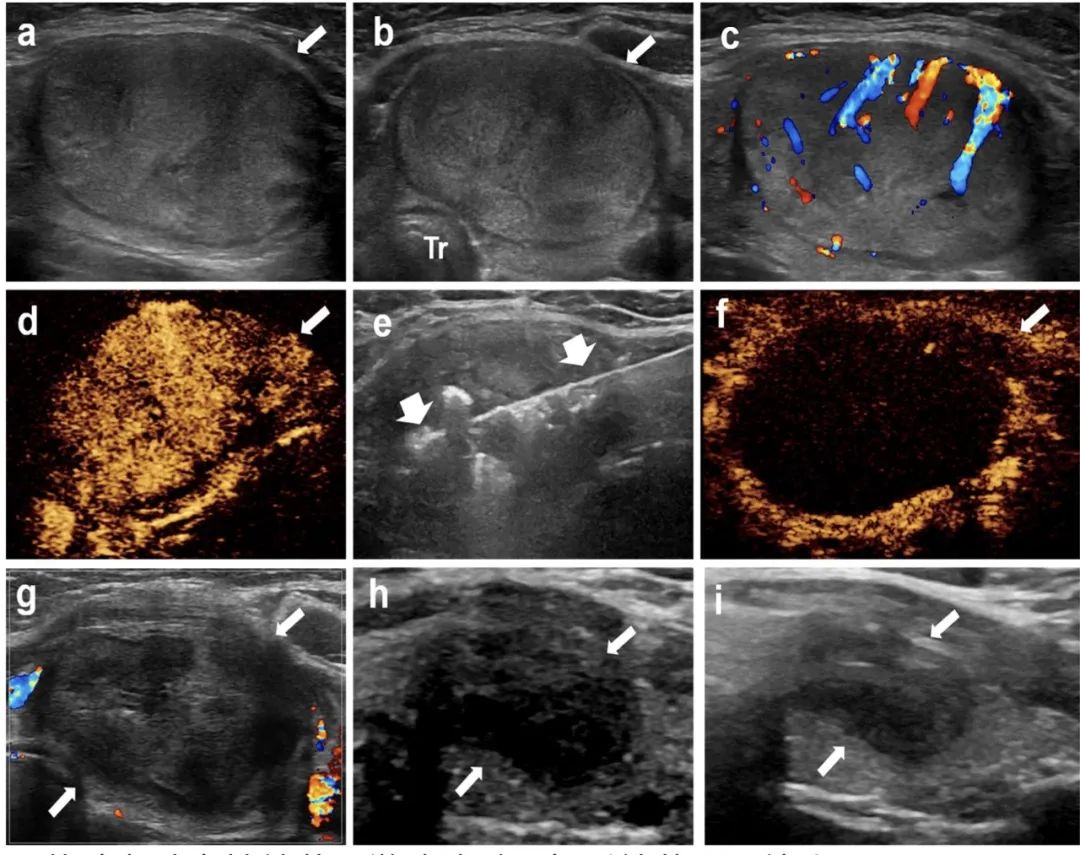

甲狀腺左葉實(shí)性結(jié)節(jié),微波消融4年后結(jié)節(jié)明顯縮小

針對(duì)該問題,石文媛主任團(tuán)隊(duì)開創(chuàng)性地將微波消融技術(shù)應(yīng)用于兒童良性甲狀腺結(jié)節(jié)的治療。連續(xù)分析了2018年1月至2021年12月在北京兒童醫(yī)院接受經(jīng)皮微波消融治療的有癥狀良性甲狀腺結(jié)節(jié)患兒25名,共 34枚結(jié)節(jié)。所有患兒均隨訪半年以上(中位隨訪時(shí)間12個(gè)月,范圍6 - 48個(gè)月)。結(jié)果顯示:經(jīng)皮微波消融治療后,結(jié)節(jié)體積逐漸減?。ㄎ⒉ㄏ谇爸形惑w積5.86 mL,末次隨訪評(píng)估中位體積0.34 mL),末次隨訪評(píng)估體積縮小率達(dá)到85.03%,技術(shù)有效率達(dá)91.2%。結(jié)節(jié)相關(guān)壓迫癥狀、美容相關(guān)問題均得到顯著改善。術(shù)后一個(gè)月隨訪甲狀腺功能維持在正常范圍之內(nèi),提示微波消融在滅活甲狀腺結(jié)節(jié)的同時(shí)不影響正常甲狀腺功能。